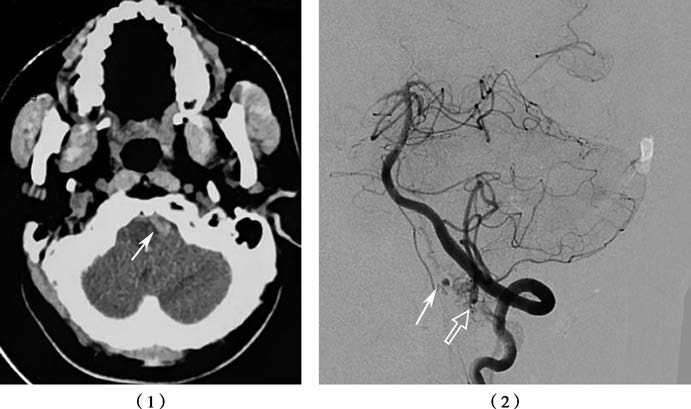

Figure 2 Subarachnoid hemorrhage, associated with spinal anterior artery aneurysm and vascular malformation

(1) CT image showing a small subarachnoid hemorrhage on the left anterior side of the medulla oblongata (arrow).

(2) Spinal anterior artery aneurysm (solid arrow), associated with vascular malformation (hollow arrow), as shown on imaging.